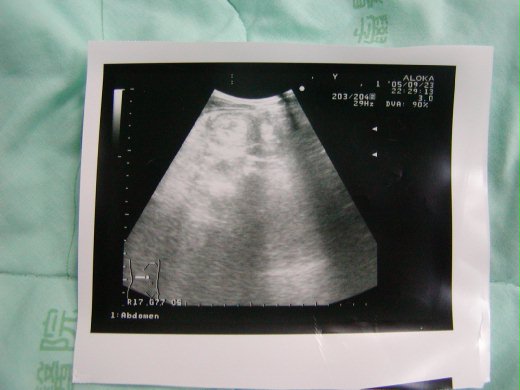

從九月21晚上開始,他告訴我肚子有點痛,我心想:「不會吧!」上完廁所以後就好多了,雖然晚上睡得不是很安穩,並沒有出現很嚴重的症狀,22、23日白天都還能去上學,直到23日下午下課後,精神顯得有一點疲倦,還會出現間歇性的疼痛,因為有三年前的經驗,就直覺情況不太妙,懷疑有腸套疊的可能性,勉強他吃完晚餐以後就帯到醫院掛急診檢查,問診填的就是「疑似腸套疊」,值班醫生還起初還不敢斷定,先是讓他照X光,本來他很勇敢,要自己一個人在放射室,在最緊要關頭竟放聲大哭起來,等待的同時和他溝通,「等一下媽媽陪你進去,你要乖乖照相,相片會在電腦送到醫生叔叔那裡,你就可以看到你的肚子,還有上面的小排骨喔,本來大人不能進去,可是醫生說你很乖,才讓媽媽進去陪你。」「可是他們大人有進去啊」「因為他們和你一樣都很不舒服,所以才要進去,你看他們都是一個人進去,對不對」點頭:「因為你是我的媽咪,所以他們才讓你進去哦?」「對啊」「你陪我一起照。」「不行,只有你才可以照,媽媽只能陪你而已,不能照。」終於說服了他,像老鳥一樣,一進去就把兩手張開,貼近面板,終於順利的趙完X光。片子顯示有宿便,通浣腸之後還是直叫肚子痛,接著才照超音波,起先他非常抗拒,一直想擦掉塗抹在身上的液體,等到他看到超音波影像時,醫生告訴他有問題的地方,就是左上角那個長的有點像甜甜圈的圖案,他才停止哭泣,還向醫生要了一張回家作紀念。

接下來更困難的工作就是要和他進行灌腸的溝通,我拿著相片告訴他:「你有沒有看到那個甜甜圈?」他點點頭。繼續說:「有一隻蟲長在裡面,我們請醫生把他抓出來好不好?」他點點頭。「等一下醫生會用一條小管子從屁股插進去,把蟲蟲吸出來,可是你要和醫生合作,才可以順利的把他抓到哦」「蟲蟲是不是在那個骨頭的地方?」他形容那個黑點為骨頭。「對啊,就是他害你肚子一直痛的。」我這個媽也太會掰了,為了讓整個過程順利進行,什麼故事都要編得出來。